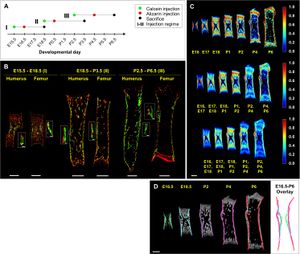

- 3.17 Isometric Scaling in Developing Long Bones Is Achieved by an Optimal Epiphyseal Growth Balance